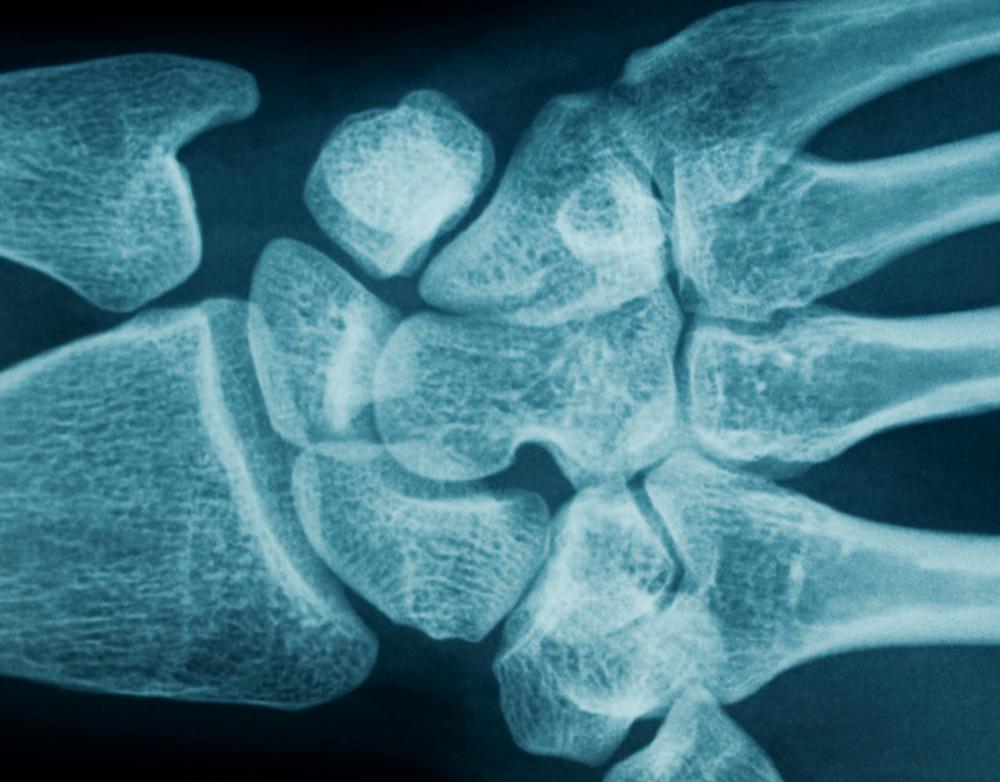

Wrist Joint FractureTypesCausesSymptomsTreatmentMedications, PT